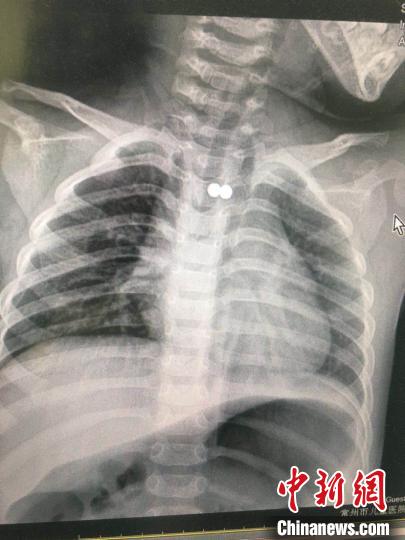

x光片顯示信息,患者身體有二顆磁力珠 唐娟 攝據了解,常州市兒童醫院2020年已相繼接診多例誤吞磁力珠就診的小孩。徐岳說:“磁力珠闖禍早已并不是第一次了,它樣子精巧,表面滑潤,非常容易被兒童誤食。進入體內后,會導致腸梗阻、腸穿孔,乃至很有可能造成 血管壁萎縮后大出血,比較嚴重時還會繼續嚴重危害性命,以前大家兒普外就接診過那樣的病歷,小朋友盡管最終命挽救了,但卻手術治療摘除了一部分腸管。”他提示眾多父母,除開磁力珠,近些年醫師從患者消化系統內取出的臟東西有棗核、硬幣、玻璃珠、筆帽、小開卡、紐扣電池、各種各樣小玩具小零件等。父母在為小孩購買小玩具時要有安全防范意識,另外還要提升對少年兒童的照護。(完)

“小孩父母表明,小孩說難受時已經玩磁力珠,猜疑是誤食了。拍片子查驗顯示信息,乳房的部位有臟東西,看樣子應該是誤吞的二顆磁力珠,由于沒有顯著的喘憋紫紺,大家考慮到磁力珠在食道里。”常州市兒童醫院內鏡管理中心負責人徐岳詳細介紹說。